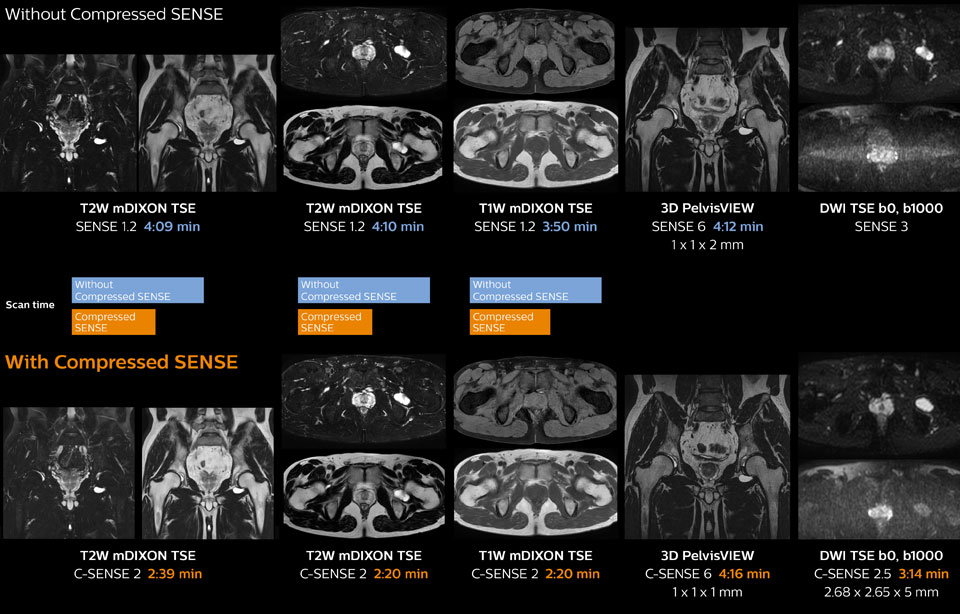

Ingenia 1.5T MRI scans with and without Compressed SENSE are compared for this case of a hip with a synovial cyst. In the mDIXON sequence, the Compressed SENSE factor used is higher than the SENSE factor on the previous scan, so scan times are reduced without sacrificing image quality. The high resolution images are useful for diagnosing of a detailed dissection. The diffusion TSE with Compressed SENSE shows reduced noise compared to the Diffusion TSE with SENSE and the artifact has disappeared.

So in this case, Compressed SENSE helped in reducing scan times of the examination. The Compressed SENSE images allowed the radiologist to confidently diagnose the lesion and see the anatomic relationships of the abnormal signal to the surrounding structures.